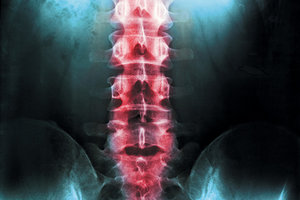

We all know it by name from anatomy class: thoracolumbar fascia (TLF) – that amazing white stuff bridging the gap between the upper and lower torso. You had to dissect and identify it in anatomy lab to pass the course.

The thoracolumbar fascia is a vitally important area for treatment of musculoskeletal injury / pathology and when developing a long-term strategy for recovery / regeneration treatment protocols. Let's review important factors regarding the TLF in relationship to movement, and offer some therapy strategies to improve efficiency and function.